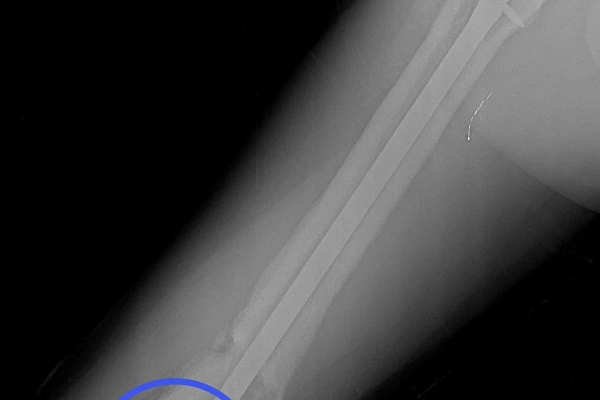

17‑летний Николай поступил к нам с осложнением после операции по поводу перелома бедра. Ранее ему был установлен интрамедуллярный штифт – для фиксации отломков кости с возможностью ранней нагрузки на конечность. Но прежде, чем перелом консолидировался, штифт сломался.

Врачам нужно было найти новое, более подходящее решение, при этом избежать травматичного открытого доступа и обойтись без больших разрезов. Задачу усложнял сломанный внутри кости штифт. Специального серийного устройства для его удаления малоинвазивным способом не существует. Чтобы пройти 40 сантиметров по костномозговому каналу, захватить и извлечь фиксатор, наши специалисты создали свою систему на базе имеющего набора проводников и экстракторов. Тщательное предоперационное планирование принесло желаемый результат в ходе вмешательства.

После успешного удаления прежней конструкции пациенту установили новую надежную систему - с учётом предыдущего опыта. Для этого понадобилось несколько небольших разрезов (не более 2 см). На второй день после операции Николай передвигался по отделению с помощью костылей, уже нагружая оперированную конечность. Сейчас он внимательнее прислушивается к рекомендациям, от выполнения которых зависит благополучие восстановительного периода.